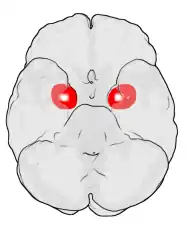

Миндалевидное тело (лат. corpus amygdaloideum), ами́гдала[1] — область мозга миндалевидной формы, находящаяся в белом веществе височной доли полушария под скорлупой, примерно на 1,5—2,0 см сзади от височного полюса. В мозге два миндалевидных тела — по одному в каждом полушарии[2]. Миндалевидное тело играет ключевую роль в формировании эмоций, в частности, страха. У пациента, миндалевидное тело которого оказалось полностью разрушено вследствие болезни Урбаха — Вите, наблюдалось отсутствие страха[3][4][5]. Миндалевидное тело также играет важную роль в функционировании памяти, принятии решений и эмоциональных реакциях[6]. Миндалевидное тело является частью лимбической системы, относится к подкорковым обонятельным центрам.

Правое и левое миндалевидные тела различаются по функциям. Исследование показало, что электростимуляция правой миндалины вызывали негативные эмоции, преимущественно страх и грусть. Стимуляция левой миндалины, напротив, вызывала в основном положительные эмоции (счастье) и лишь изредка — отрицательные[12]. Другое исследование доказывает, что миндалевидное тело играет роль в человеческой системе самопоощрения[13].

Кроме разницы в размерах, существуют другие различия между полами. Была изучена активация миндалевидного тела при просмотре фильмов ужасов у мужчин и женщин. Результаты исследования показали, что у разных полов активируются различные полушария. Повышенная активность наблюдалась у мужчин в правом полушарии, в то время как у женщин — в левом[20]. Также исследования показали, что женщины в среднем запоминают эмоционально насыщенные события лучше, чем мужчины[21].